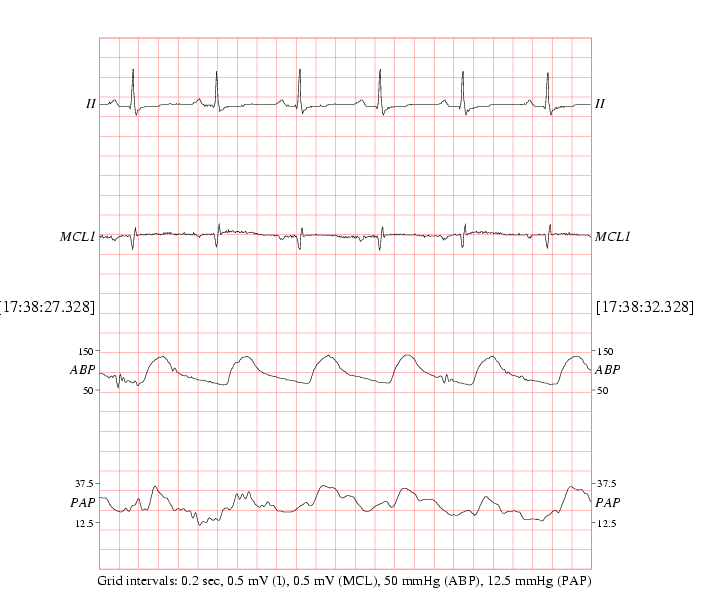

Note that we define waveforms to be rapidly sampled (125Hz) signals recorded by the bedside monitors such as electrocardiograms (ECG) and arterial blood pressure (ABP) waveforms, illustrated in Figure 1.2. We define trends to be a time series of parameters derived from the waveforms by the bedside monitors, such as heart rate, systolic blood pressure, cardiac output and relative oxygen saturation. Of course, time series of repeated clinical measurements are also found in the relational database, such as pH levels, laboratory values and administered medications.

Figure 1.2: Typical clean waveform data in the MIMIC II database. From top to bottom: Two leads of ECG (II and MCLI), arterial blood pressure (ABP) and pulmonary arterial pressure (PAP).